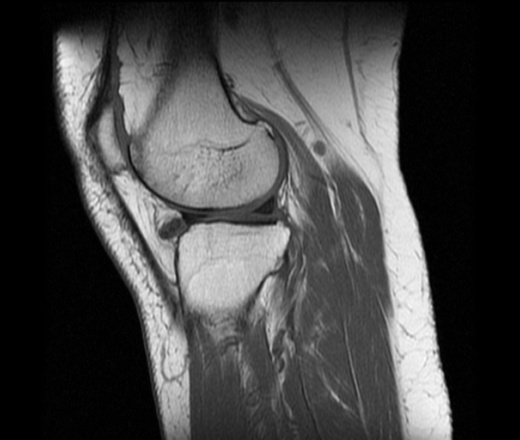

Новообразование коленного сустава ? Коллеги, помогите разобраться, пожалуйста. В передних отделах коленного сустава, спереди от передней интерменисковой связки визуализируется структура, имеющая низкий МР-сигнал во всех последовательностях (Т1-, Т2-ВИ, PD FSEFatSad). Что это может быть?

По клинике: неудачно наступила, почувствовала щелчок. Жалуется на отек коленного сустава. Из сопутствующих патологий на МРТ выявила: ДОА, разрыв заднего рога и тела мед.мениска. Бурсит. Синовит.

Виллонодуллярный синовиит?

Жалобы у пациента есть? Предположил бы хондроматоз.

Вероятно, хондральные тела.

Соглосна, похоже на то!